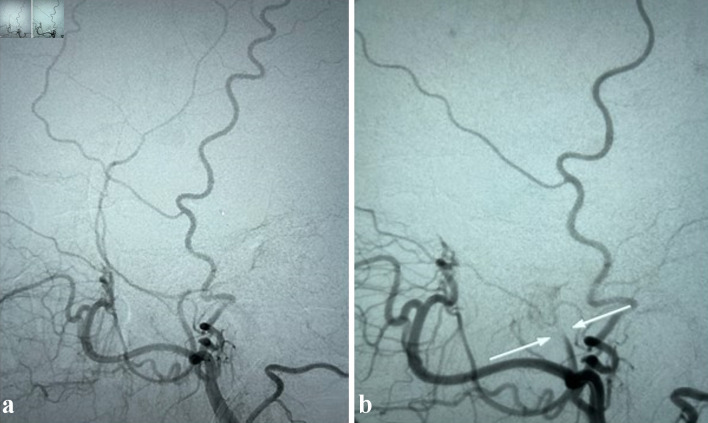

Intracerebral hemorrhage is a potentially fatal complication in patients with acute leukemia and contributing factors include thrombocytopenia and coagulopathy. Patients with acute leukemia may develop subdural hematoma (SDH) spontaneously or secondary to trauma. In patients with acute leukemia and SDH, the surgical evacuation of the hematoma causes significant morbidity and mortality. New approaches and strategies to reduce the need for surgical evacuation are needed to improve outcomes in patients with acute leukemia and intracerebral hemorrhage. We report two cases of acute SDH in patients with acute leukemia successfully treated with middle meningeal artery embolization, a minimally invasive interventional radiology technique, obviating the need for a surgical intervention. The first patient with acute promyelocytic leukemia (APL) presented with coagulopathy and developed an acute SDH after a fall. The second patient with acute myeloid leukemia presented with gum bleeding and also sustained an acute SDH after a fall. Both patients underwent middle meningeal artery embolization for treating their SDHs while actively receiving induction chemotherapy for acute leukemia. Both patients had resolution of their acute SDH and are in remission from their acute leukemia. Middle meningeal artery embolization is a very effective, and within the context of this setting, a novel, minimally invasive technique for management of SDH in acute leukemia patients, which can prevent the need for surgical interventions with its associated comorbidities and high risk of fatal outcomes in patients with acute leukemia and acute SDH.

Abstract Image